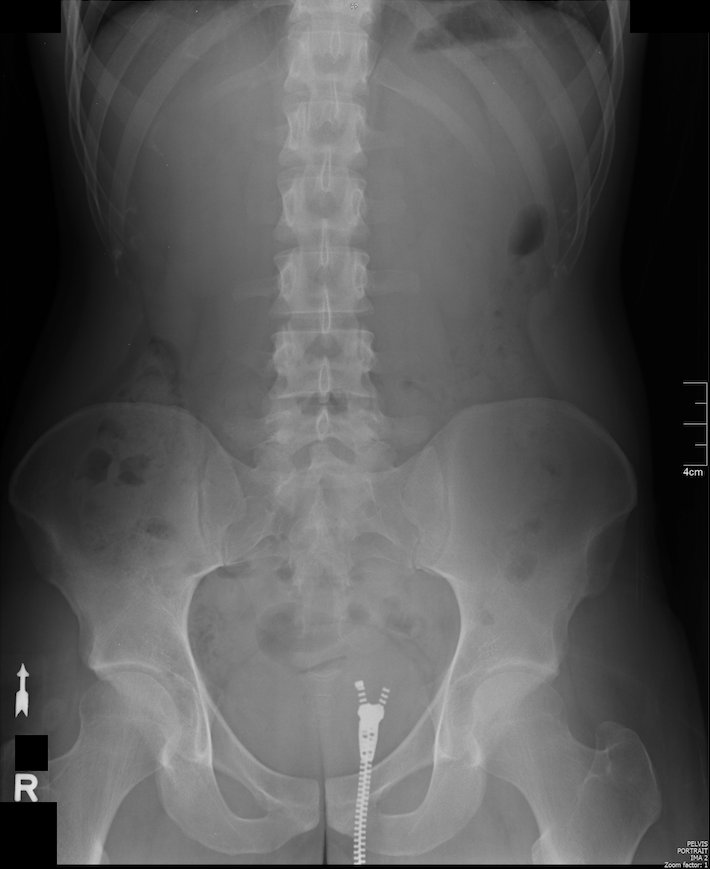

Provided are 2 radiographs: One PA chest & one AP pelvis. Attempt to interpret them to the best of your abilities (hopefully using my tutorial for the CXR) and let me know what dysfunctions/anomalies you find in the comment section below. Secrete nugget, they’re mine. 😉 Happy huntings!

P.S. I found 4…